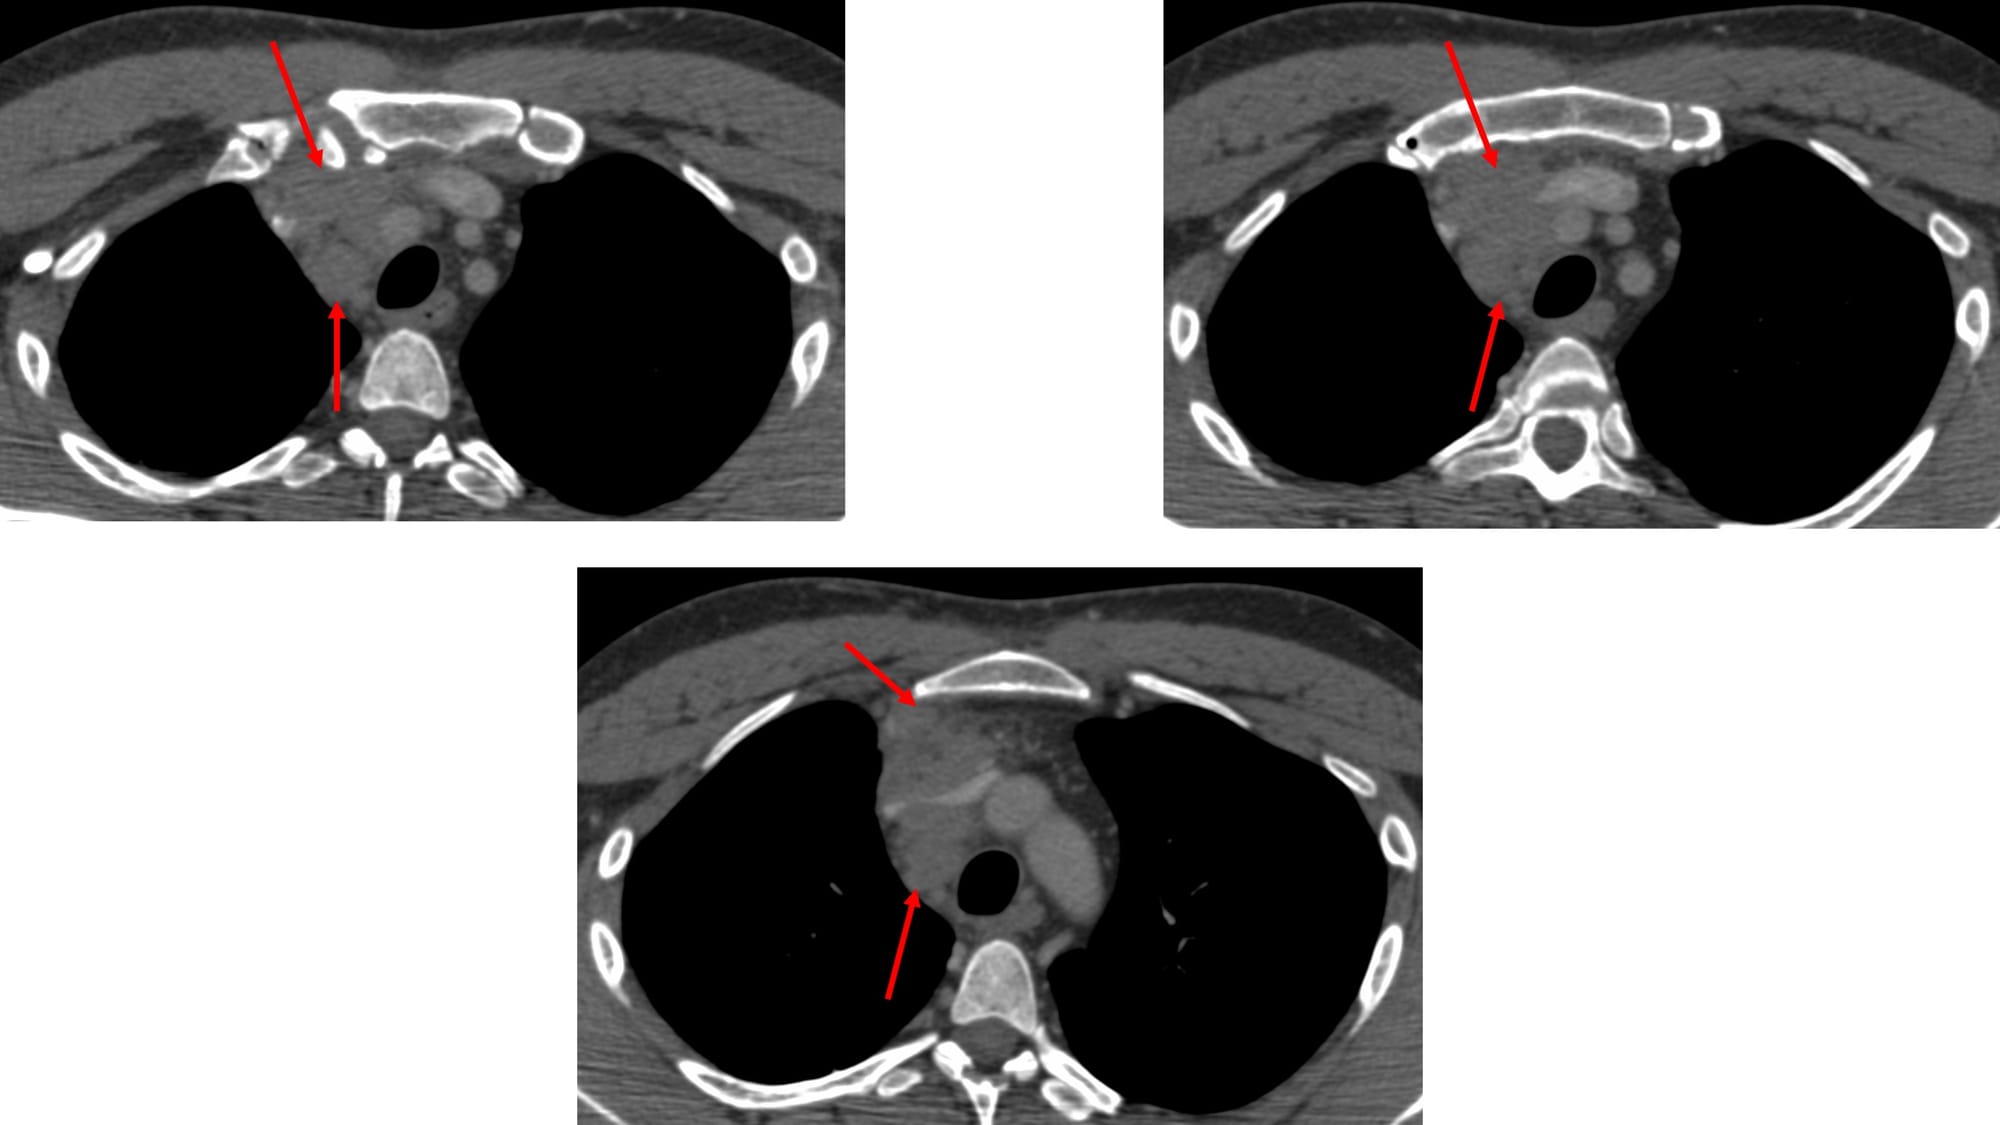

A 46-years old presented with a prevascular space nodal mass extending into the middle mediastinum.

A biopsy was asked for.

What route will you take?